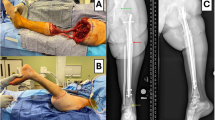

Biomechanical data were collected using an optical-based motion capture system with eight cameras (Vicon Motion System, Oxford Metrics Ltd, Oxford, UK) and a force platform system (OR6, AMTI, Watertown, USA). A total of 43 reflective markers were attached to the anatomical landmarks of each participant as shown in Fig. 1. The force platform recorded ground reaction forces during the right foot stance phase in gait, as well as forces from both feet and chair-ground contact during sit-to-stand tests, with the latter used to detect seat contact events.

Muscle activity was measured using wireless surface EMG sensors (Trigno Avanti, Delsys Inc., Massachusetts, USA) following SENIAM guidelines17. EMG signals were recorded from eight muscles of the right dominant leg: gluteus maximus (GMax), gluteus medius (GMed), rectus femoris (RF), vastus medialis (VM), vastus lateralis (VL), biceps femoris (BF), gastrocnemius medialis (GA), and tibialis anterior (TA). Prior to electrode placement, standardized skin preparation procedures were implemented, including local hair removal and alcohol cleansing to ensure good conduction. The maximal voluntary contraction (MVC) tests were performed following the guideline18 before physical performance tests to establish reference values for EMG signal normalization. Participants were instructed to perform maximal isometric contractions against manual resistance in standardized positions for each muscle, holding each contraction for 5 s with verbal encouragement to ensure maximal effort. Two trials were conducted per muscle, with 60 s of rest between trials, and the highest EMG amplitude was recorded for normalization. The motion capture, force platform, and EMG system were synchronized at sampling rates of 250 Hz, 2000 Hz and 2000 Hz, respectively.